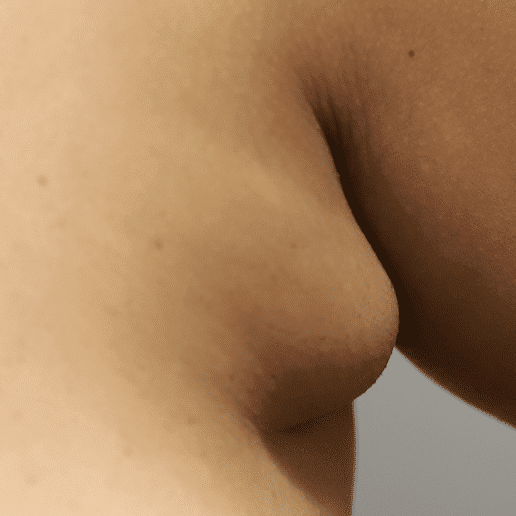

As discussed in the Pregnancy and Birth section, women may experience breast lymphedema (swollen breast) and pain, particularly during periods of early breast growth in the first trimester and in the last trimester nearing childbirth. This is more common than true gigantomastia. This discomfort is related to increase in the gland, blood vessels, and surrounding fluid. Swelling and even pitting usually is most evident in the lower part of the breast, and can be pink or mildly reddish in color. These cases also. can gain significant relief from lymphatic massage and supportive bras. Any asymmetry in presentation warrants referral to a breast surgeon to evaluate for breast masses and/or inflammatory breast cancer.